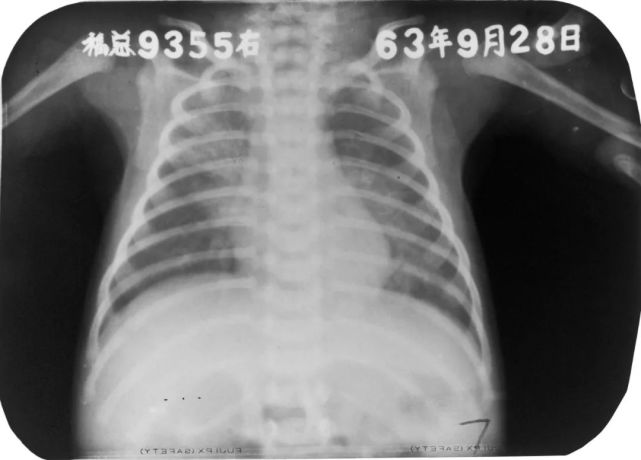

婴幼儿肺炎

图片

胸部正位片示:两肺内带及左肺下野可见不规则的小片状或斑片状边缘模糊的致密阴影,阴影密度不均,局部可见支气管充气征